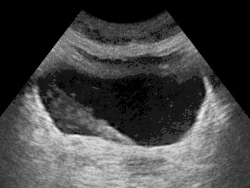

Der klinischen Untersuchung ist der Harnleiter kaum zugänglich, auch auf einer normalen Röntgenaufnahme stellt er sich nicht dar, lediglich röntgendichte Harnleitersteine werden abgebildet. Deshalb werden bei der Urografie meist intravenös verabreichte Kontrastmittel verwendet. Diese werden über die Niere ausgeschieden, gelangen so in die Harnleiter und kontrastieren diese. Hiermit lässt sich der Harnleiter in seiner gesamten Länge darstellen. Die Urografie ist, nicht zuletzt wegen der Gefahr von Nierenschädigungen, durch andere bildgebende Verfahren weitestgehend ersetzt worden und wird heute vor allem noch zur Diagnostik von Harnleitersteinen angewendet. Die Darstellung des Harnleiters mittels Ultraschall gelingt meistens nur bei Stauungen (Ureterozele). Die Computertomografie (CT) wird in Niedrigdosistechnik oder als CT-Urografie, also mit Kontrastmittelverabreichung eingesetzt. Sie ist im Nachweis von Harnleitersteinen verlässlicher als die herkömmliche Urografie und kann auch zur Klassifikation und Stadienbestimmung in der Onkologie verwendet werden. Die Magnetresonanztomographie (MRT) hat eine ähnliche diagnostische Aussagekraft und ist besonders dann angezeigt, wenn eine Kontrastmittelgabe wegen Unverträglichkeit nicht möglich ist.[50]

Die Ureterozele ist eine zystische Erweiterung des blasenseitigen Abschnitts des Harnleiters. Sie tritt bei einem von 4.000 Kindern auf, häufiger bei Mädchen und zumeist im Bereich des linken Harnleiters. Häufig liegt gleichzeitig eine Doppelniere vor. Die Ureterozele kann einen Rückstau des Urins und schließlich eine Wassersackniere verursachen.[70] Ein Megaureter, eine Erweiterung des Harnleiters auf mehr als 7 mm, tritt bei einer von 6.500 Lebendgeburten auf. Die Ursache ist unbekannt. Er kann infolge von Harnblasenerkrankungen mit Abflussstörung auch nach der Geburt entstehen. Der Megaureter zeigt sich durch Bauchschmerzen und Blut im Urin.[71]